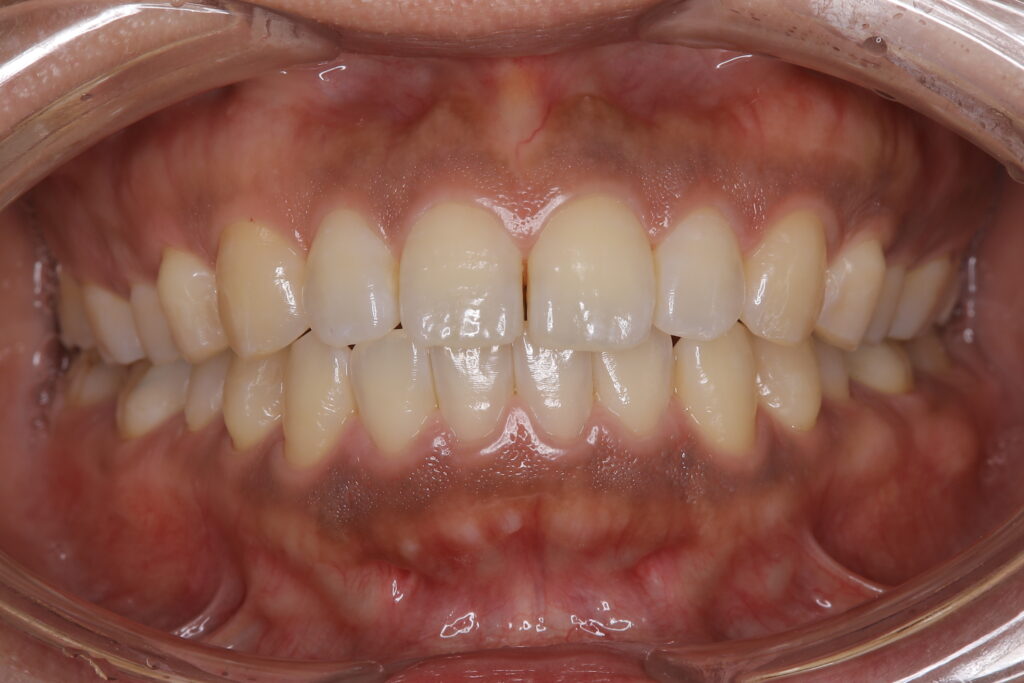

歯グキがピンク色になると、

ハイライト効果で歯も明るく見えます!

見た目の印象も大違いなのでお勧めの施術です👌

赤みも落ち着いて綺麗なピンク色になりました🌟